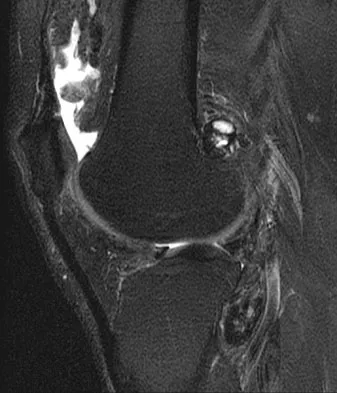

A 28-year-old man reports knee stiffness, swelling, and a constant ache that is worse with activity. Examination reveals an effusion, global tenderness, and warmth to the touch. Flexion is limited to 110 degrees. Figures 48a through 48d show sagittal T1-weighted, sagittal T2-weighted, axial T1-weighted fat-saturated gadolinium, and axial gradient echo MRI scans. Based on these findings, what is the most likely diagnosis?

Figure 48 shows an MRI scan of the knee. The arrow is pointing to what structure?